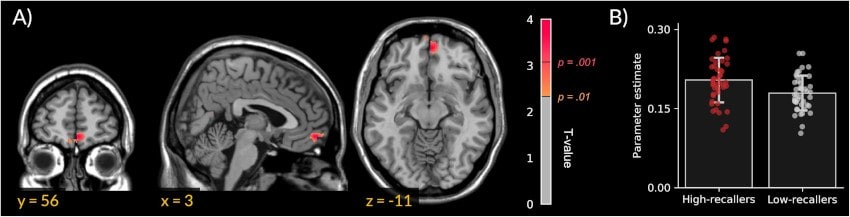

In 2018, the same team linked frequent recall to denser white matter in the medial prefrontal cortex among 'big dreamers.' This region aids dream generation more than storage, with no differences in amygdala or hippocampus.